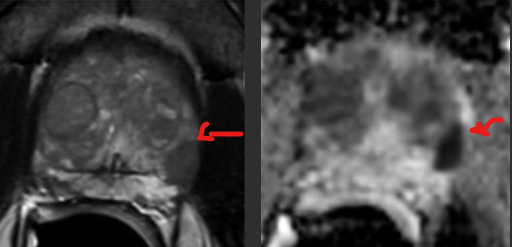

PI-RADS 5.

ADC axial mostra sinal marcadamente diminuído (esquerda). A imagem correspondente em DWI mostra sinal marcadamente aumentado. Escore PI-RADS DWI foi 5. Escore PI-RADS global é 5. Biópsia revelou câncer com Gleason 4+3 (grupo de grau 3).